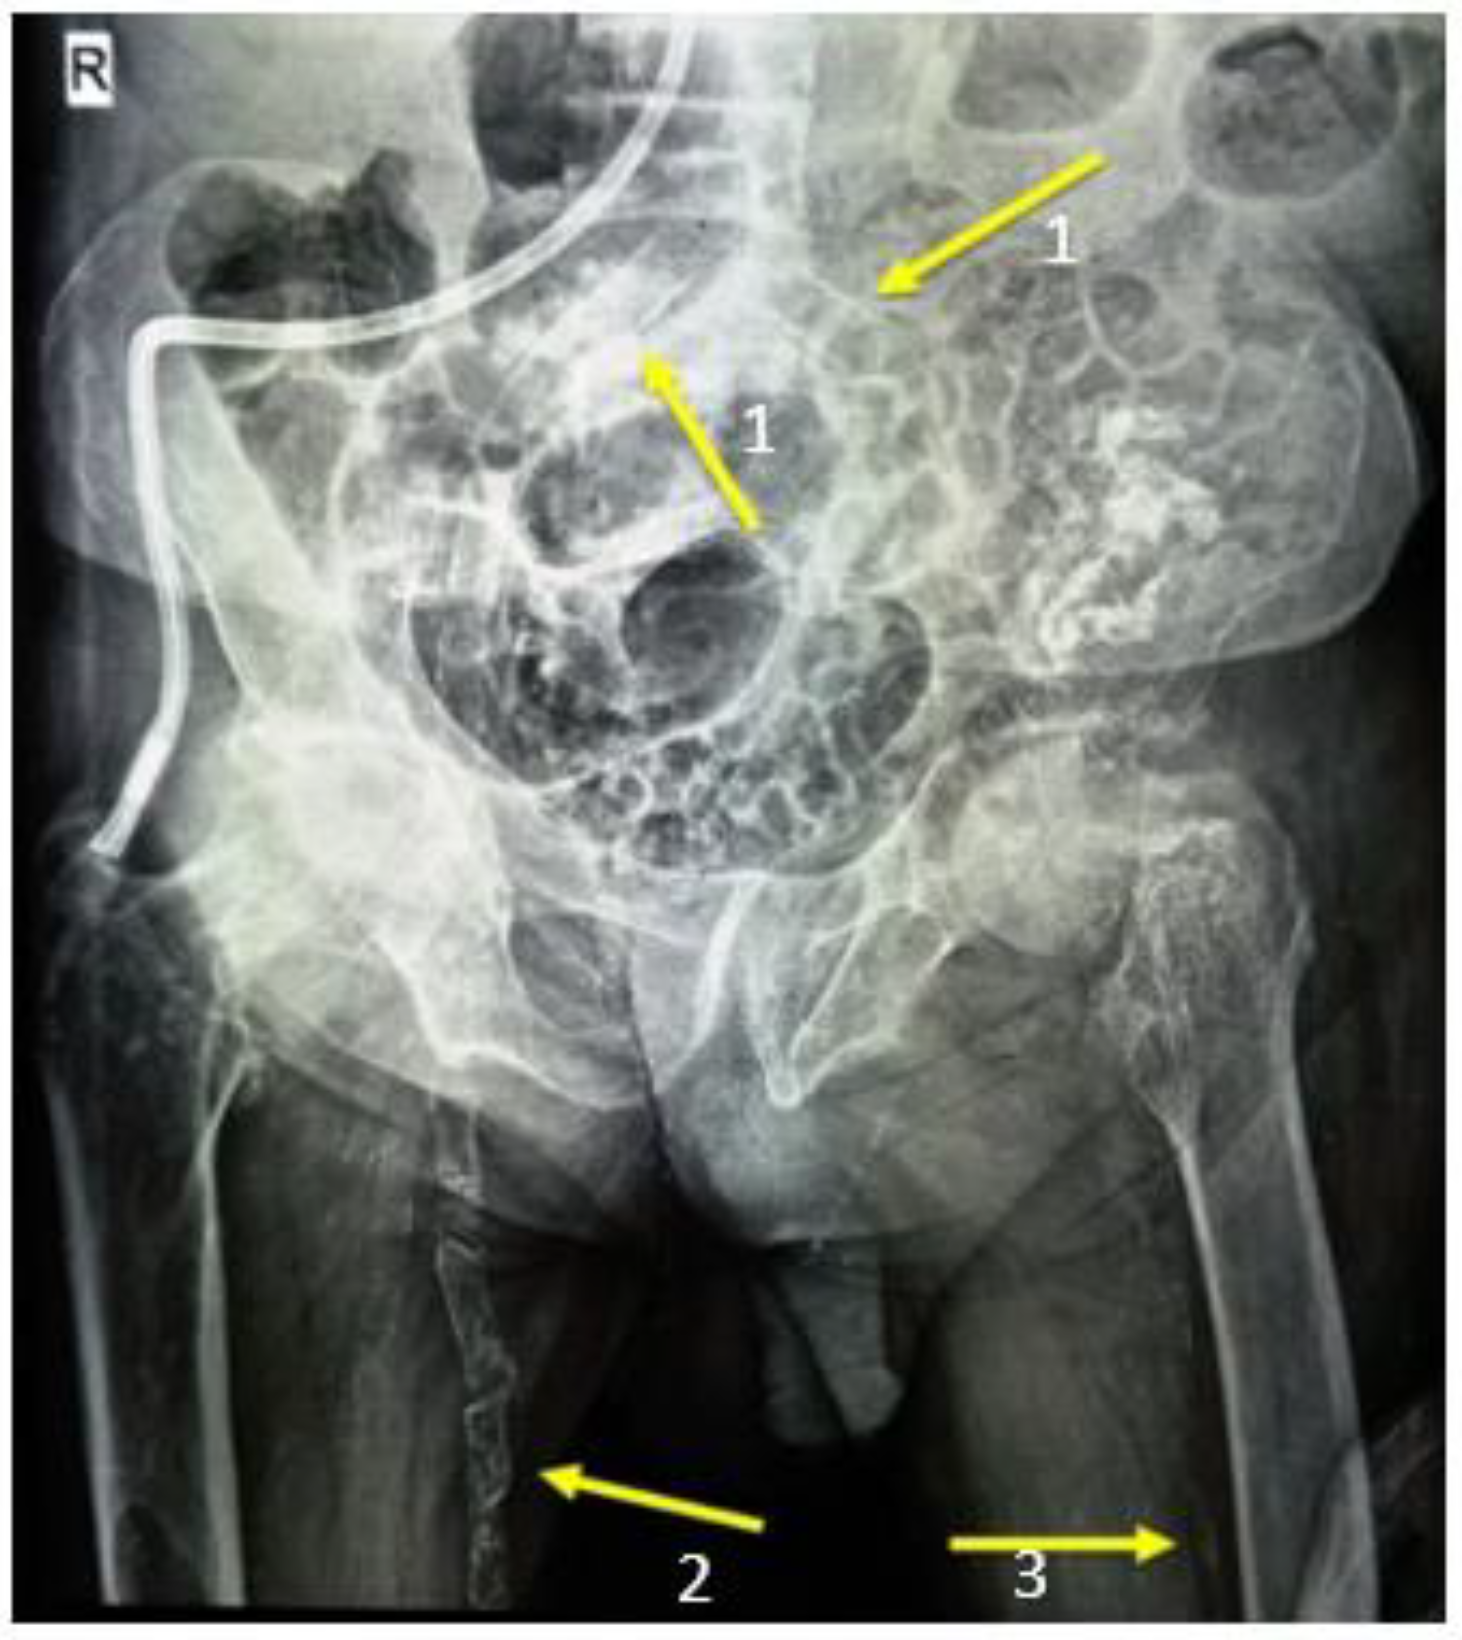

3. Paraclinical Aspects